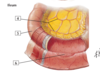

5

5 - internal thoracic vein

6

6 - inferior epigastric veins

7

7 - superficial epigastric vein

8

8 - superficial epigastric vein

9

9 - thoraco-epigastric vein

10

10 - lateral thoracic vein

11

11 - jugular veins (external, internal, anterior)